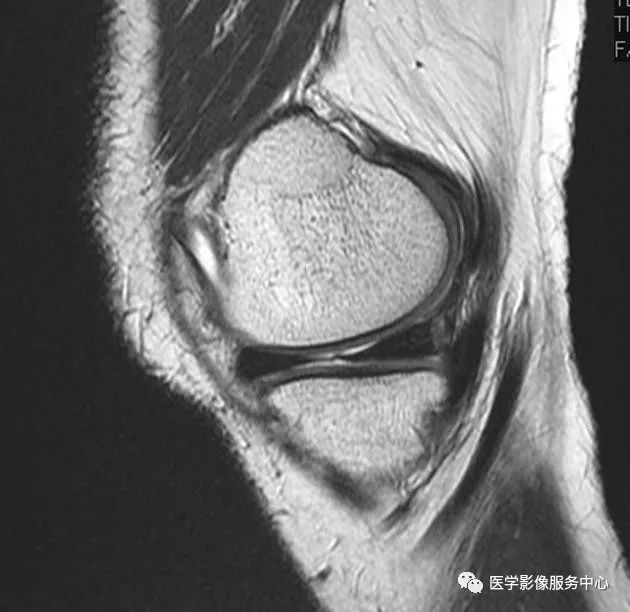

在T1加权矢状图像上,可见骨化(箭头)位于内侧半月板的后角内;